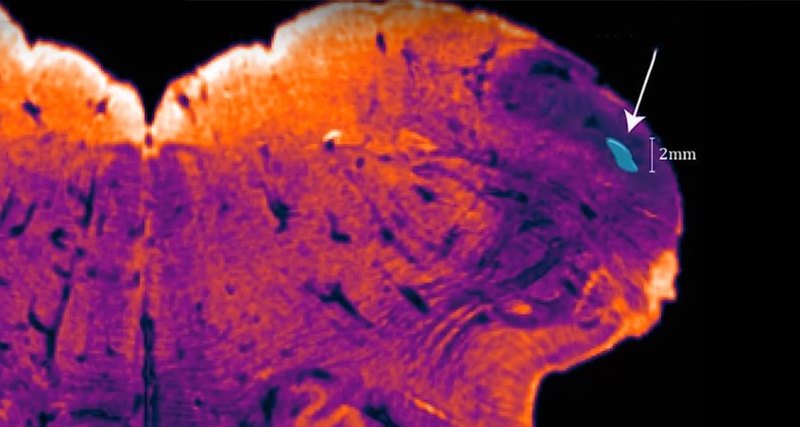

It’s about the size of a pea and sits at the back of the skull, right at the base of the brain. Its discoverer, NeuRA’s brain cartographer Professor George Paxinos, has christened it the Endorestiform Nucleus.

His newly-found region is embedded in a major neural highway that links the spinal cord and the brain. This part of the brain is known to be involved in how we control the movement of our limbs and body.